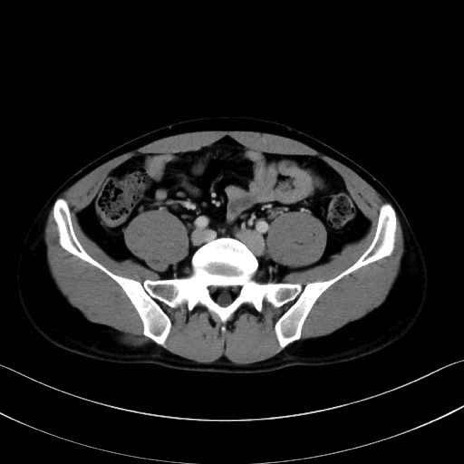

大腰筋 (Psoas major)

腸骨筋 (Iliacus)